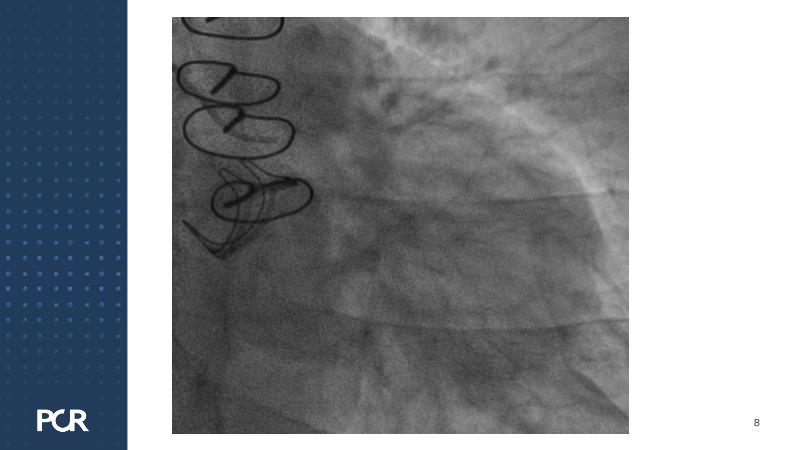

Watch this session focused on a patient with distal left main stenosis to understand that the stepwise provisional side branch (SB) stenting strategy is the standard approach for most left main trifurcation lesions. Discover the importance of optical frequency domain imaging for strategy determination and bifurcation PCI outcome optimization. Learn about the Ultimaster Nagomi™ DES, inheriting features from the Ultimaster Tansei™ stent, tailored for complex bifurcation anatomy with enhanced deliverability and overexpansion capacity.